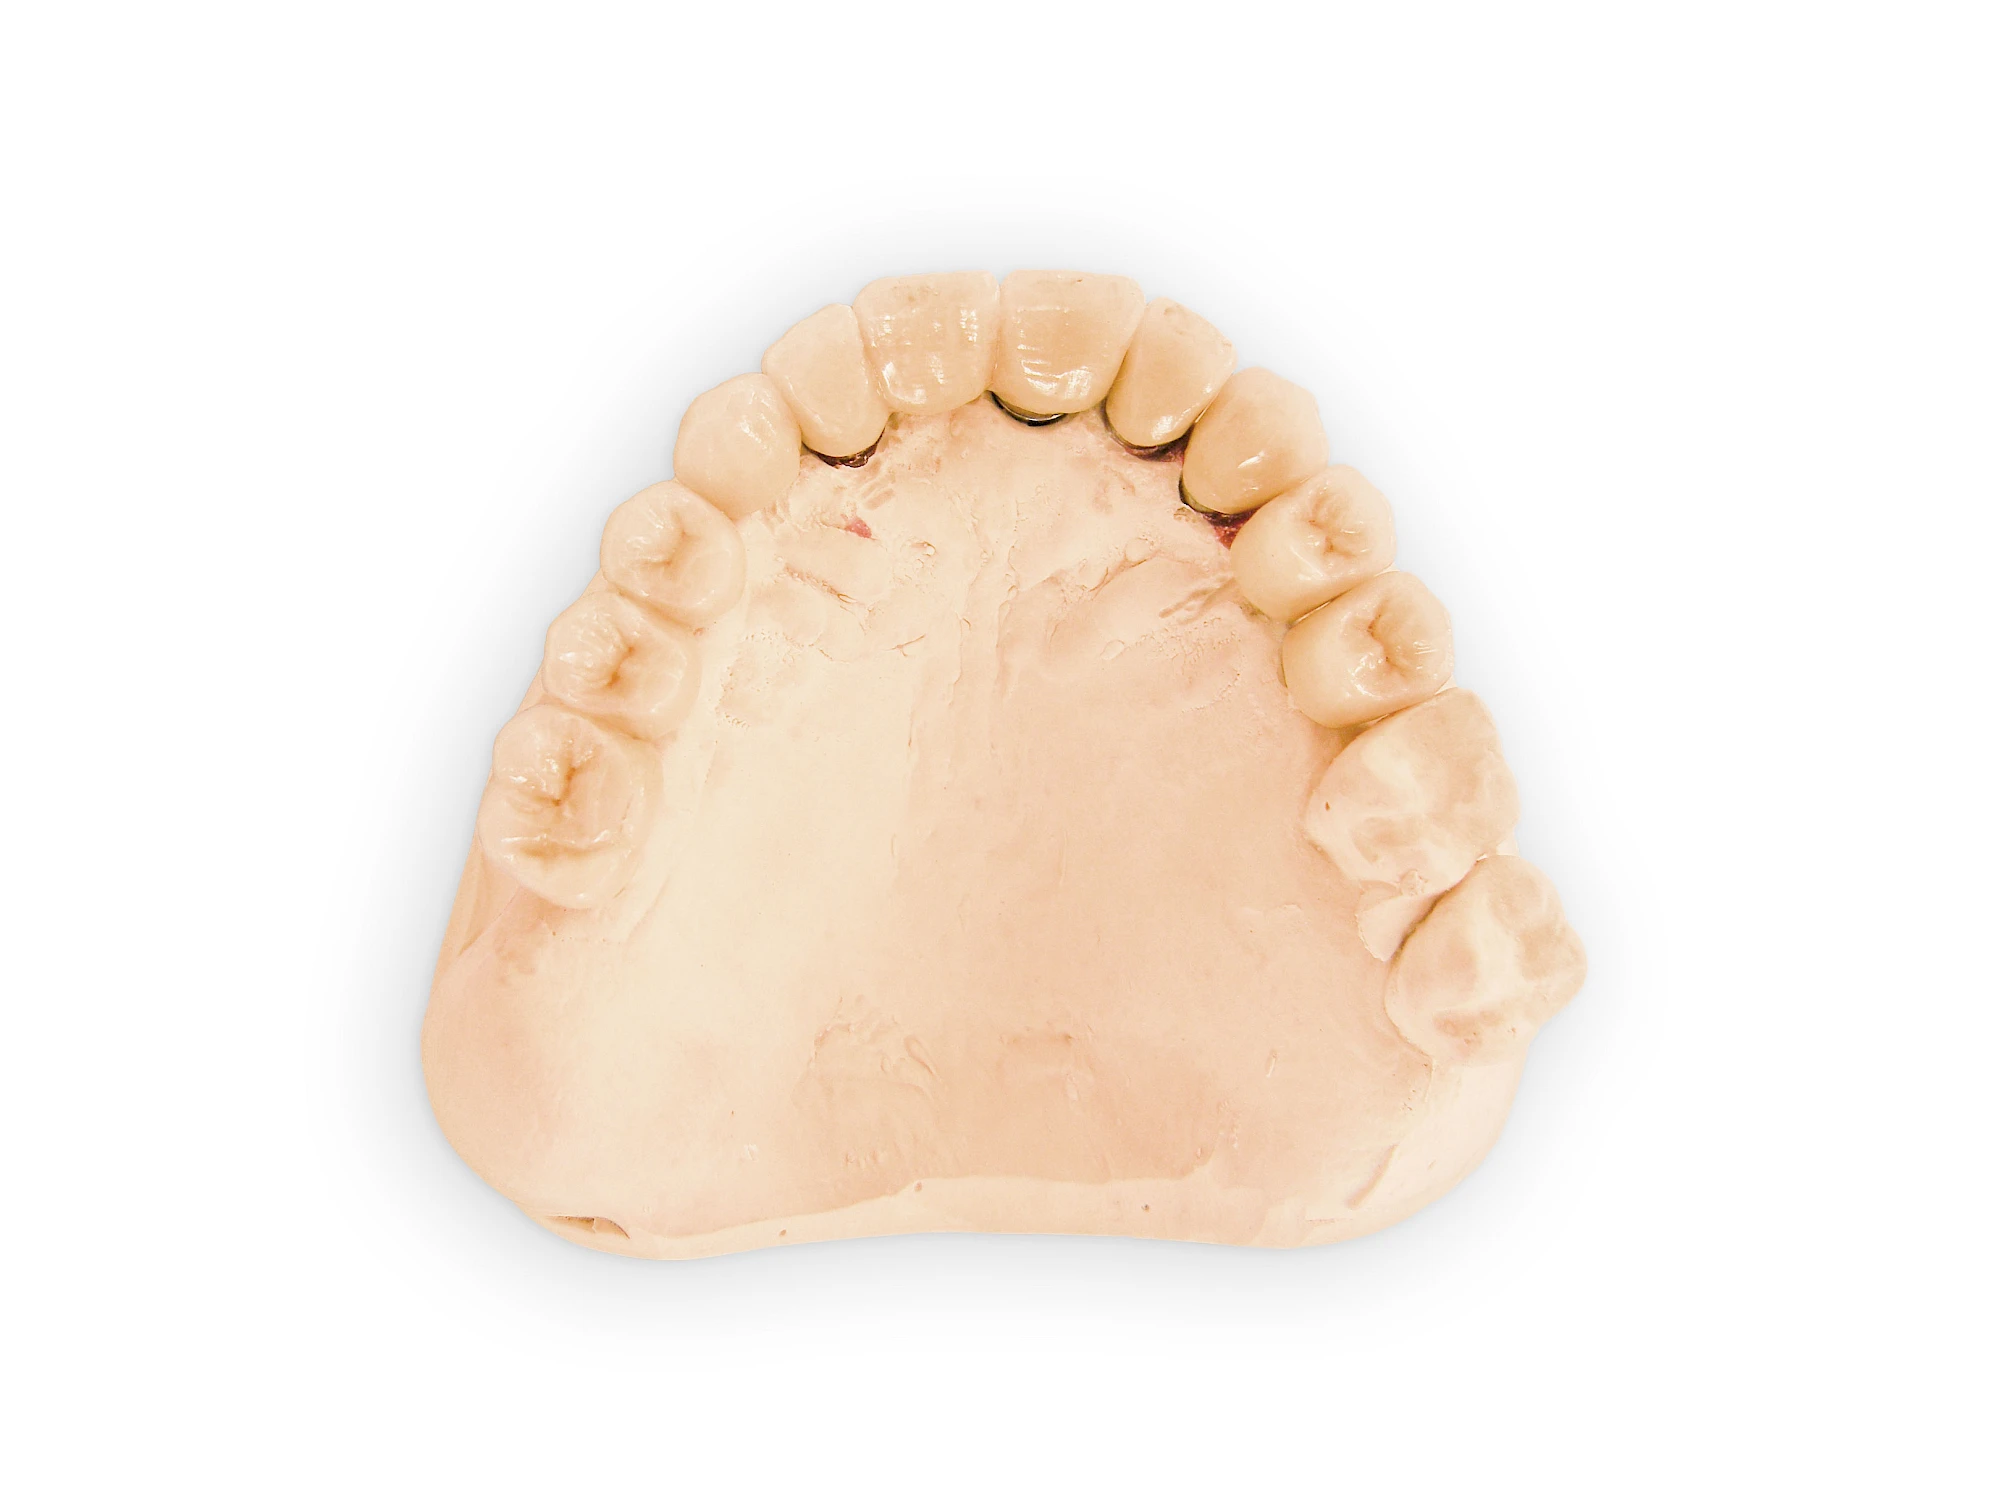

Fehlen einzelne Zähne und die Nachbarzähne sind unbeschadet oder gut zahnärztlich versorgt, werden immer häufiger Implantate gewählt, um die Lücken zu schließen. Auch bei größeren oder verteilten Lücken, wenn keine herausnehmbare Prothese gewünscht ist, werden Implantate für Kronen- bzw. Brückenversorgungen gesetzt. In Einzelfällen entscheiden sich sogar zahnlose Patienten für eine festsitzende Versorgung auf Implantaten.

Varianten zur Verankerung von festsitzendem Zahnersatz auf Implantaten